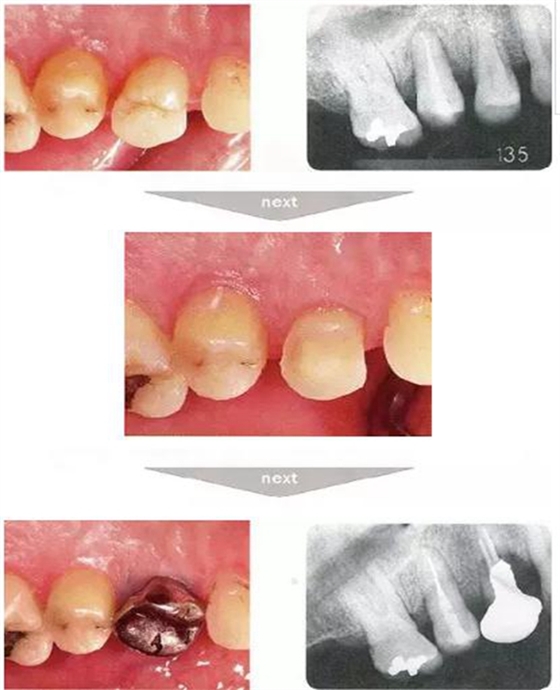

右下4牙冠牙根破折案例。照片是破折前4個(gè)月拍攝的。牙周袋深度為3mm以下,牙周組織為正常狀態(tài)(右下5是以前由智齒矮小齒移植而來)。破折后,舌側(cè)咬頭破折至傾斜的牙根處,破折片與牙齦相連。

去除破折片進(jìn)行了修復(fù)治療。3年后,上頜腭側(cè)有6mm、近中有4mm的牙周袋。X片可觀察到嚴(yán)重的骨吸收現(xiàn)象??赏茢喑鍪瞧普垡鸬母街鴨适?。